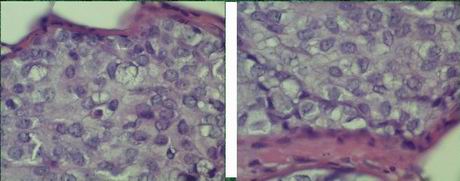

lobules distended, solidified

uniform, dyshesive, small cells

small, uniform round-to oval nuclei

+ homogenous chrom.,+/- nucleoli

nn. eccentric, cyto. pale lightly eos.

cyto. vacuoles-signet ring cell „A“

and/or

cyto. more, nn. variation, + nucleoli „B“